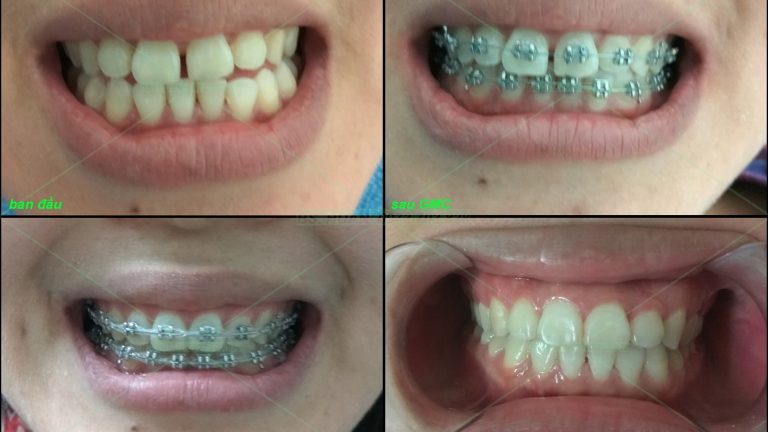

Ca này em họ vợ tôi, bắt đầu làm lúc mới học lớp 7 và vượt quãng đường 150km đều đặn hàng tháng từ Lạng Sơn xuống Hà Nội tôi chỉnh cho em, ca có nhổ 4 răng 4 trong 1 lần hẹn 1 cách khá dũng cảm. Kết quả không phụ sự kì vọng […]